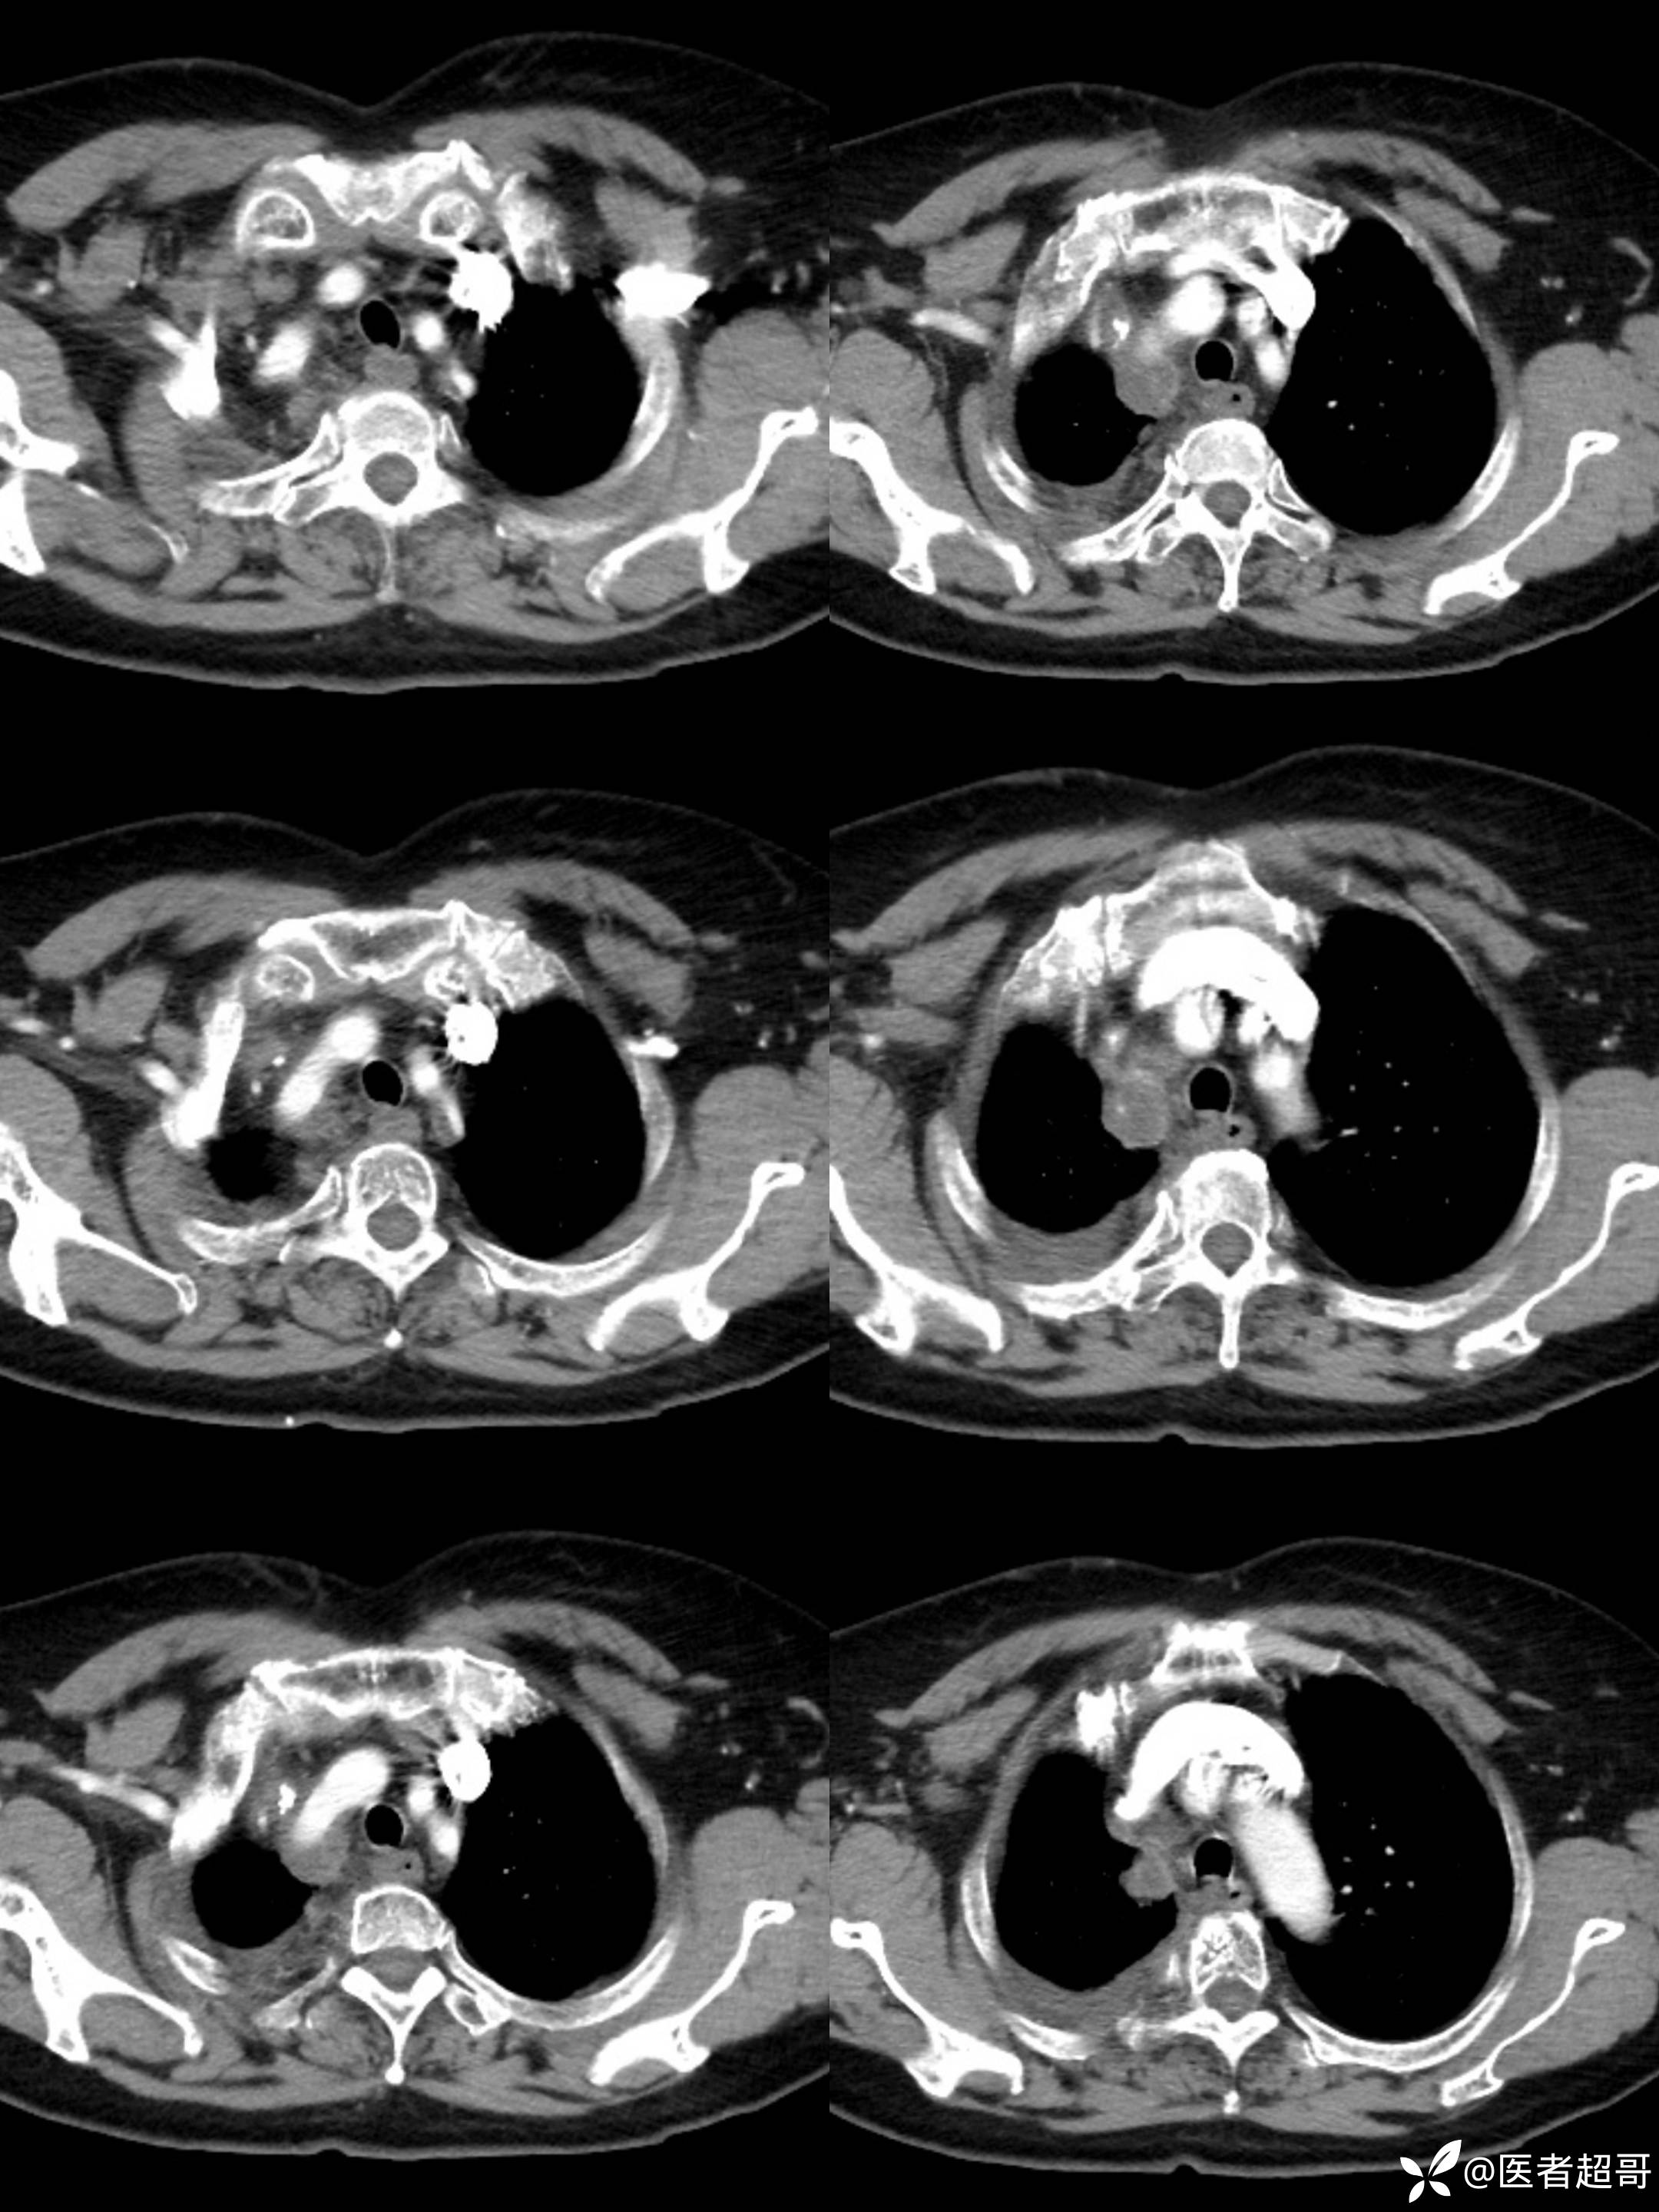

女65岁,患者于一月前无明显诱因突发右胸背部疼痛不适,呈阵发性疼痛

结核特异性细胞(TB-I) 阴性;超敏反应C蛋白(hsCR) 18mg/L ↑,其余血常规正常;

纵隔良性畸胎瘤 (1)